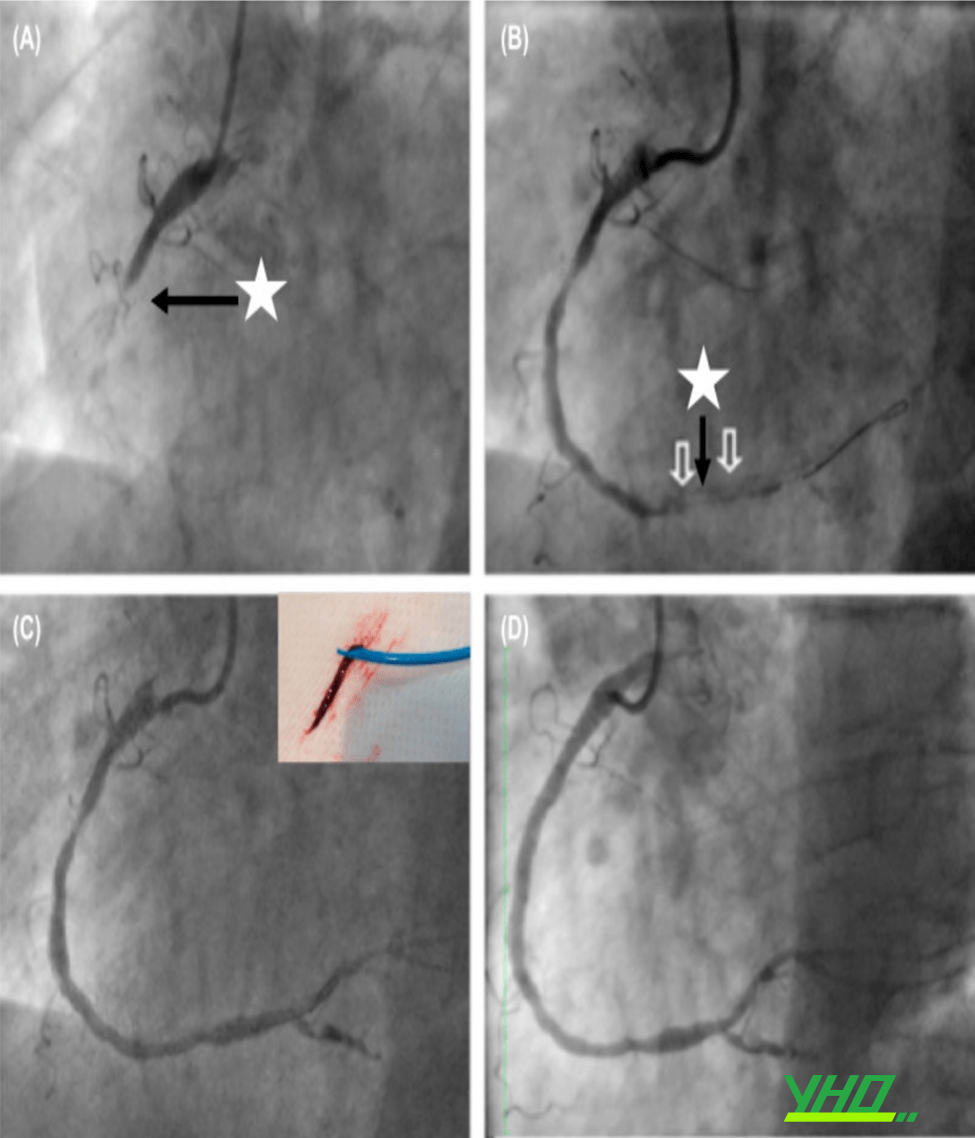

Hình 17.23. Hút huyết khối bằng ống thông với áp lực âm. (A) Hình ảnh chụp ĐMV cho thấy tắc hoàn toàn đoạn 2 ĐMV phải (mũi tên). (B) Sau nong bóng, huyết khối trôi xuống đoạn xa ĐMV (mũi tên đen và trắng).(C) Hút huyết khối bằng dụng cụ Export. (D) Đặt stent ĐMV tái thôngdòng chảy.